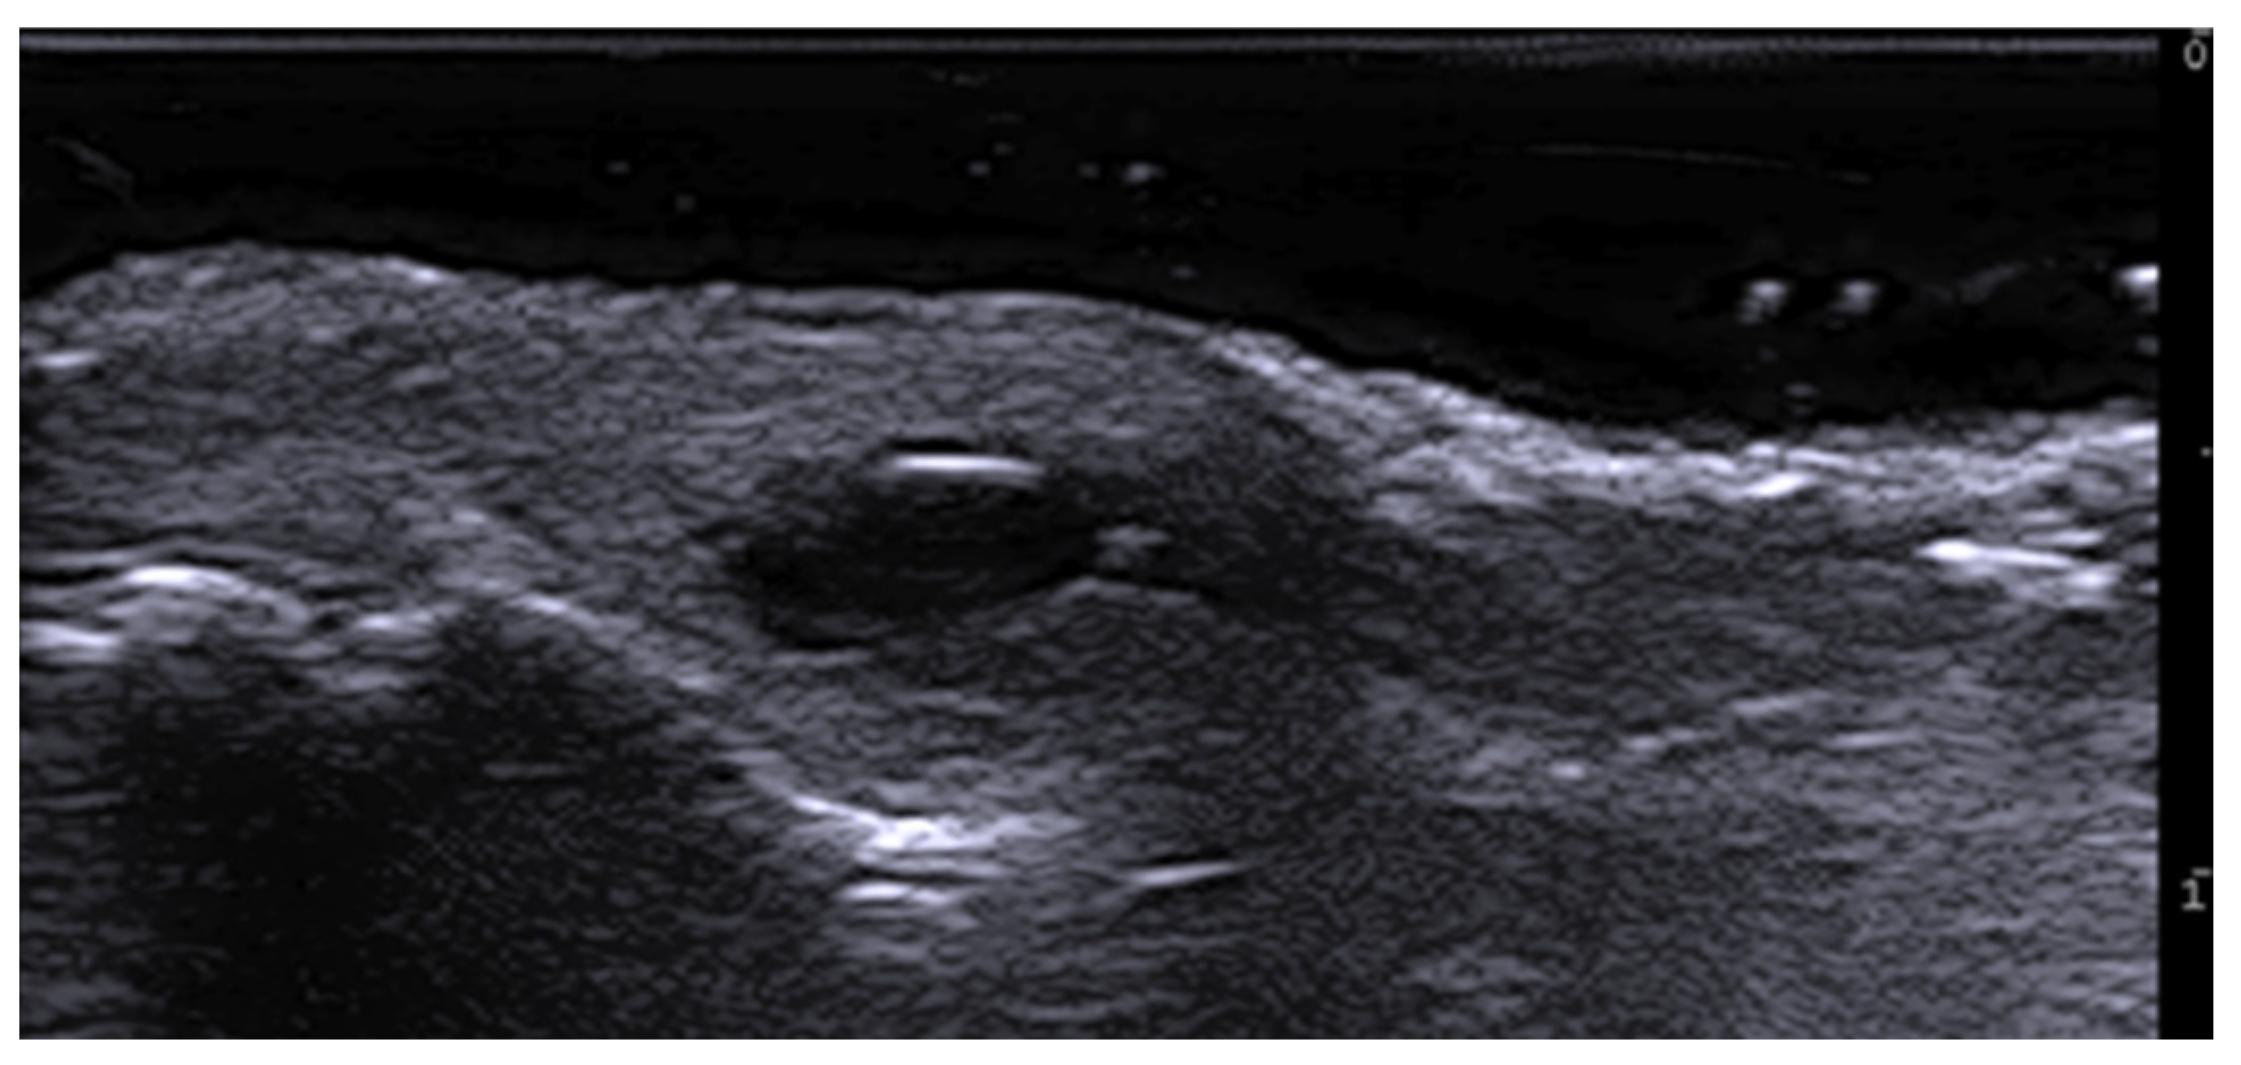

- Wortsman, X. Update on Ultrasound Diagnostic Criteria and New Ultrasound Severity and Activity Scorings of Hidradenitis Suppurativa: Modified SOS-HS and US-HSA. J. Ultrasound Med. 2024, 43, 207–213. [Google Scholar] [CrossRef] [PubMed]

- Mendes-Bastos, P.; Martorell, A.; Bettoli, V.; Matos, A.P.; Muscianisi, E.; Wortsman, X. The use of ultrasound and magnetic resonance imaging in the management of hidradenitis suppurativa: A narrative review. Br. J. Dermatol. 2023, 188, 591–600. [Google Scholar] [CrossRef]

- Iannone, M.; Janowska, A.; Oranges, T.; Balderi, L.; Benincasa, B.B.; Vitali, S.; Tonini, G.; Morganti, R.; Romanelli, M.; Dini, V. Ultrasound-guided injection of intralesional steroids in acute hidradenitis suppurativa lesions: A prospective study. Dermatol. Ther. 2021, 34, e15068. [Google Scholar] [CrossRef] [PubMed]

- Sechi, A.; Patrizi, A.; Raone, B. Intralesional steroid injections to target sinus tract fibrosis in hidradenitis suppurativa: Results from an ultrasound-based retrospective study. Dermatol. Ther. 2022, 35, e15710. [Google Scholar] [CrossRef]

- Dini, V.; Michelucci, A.; Granieri, G.; Zerbinati, N.; Margiotta, F.M.; Romanelli, M. Evaluation of post-surgical complications of hidradenitis suppurativa lesions explored with presurgical ultra-high frequency ultrasound mapping. J. Wound Care 2024, 33, S10–S16. [Google Scholar] [CrossRef]

- Michelucci, A.; Fidanzi, C.; Manzo Margiotta, F.; Granieri, G.; Salvia, G.; Janowska, A.; Romanelli, M.; Dini, V. Presurgical Mapping with Ultra-high Frequency Ultrasound of Hidradenitis Suppurativa Lesions Treated with Wide Local Excision and Secondary Intention Healing. Dermatol. Surg. 2025, 51, 36–39. [Google Scholar] [CrossRef]